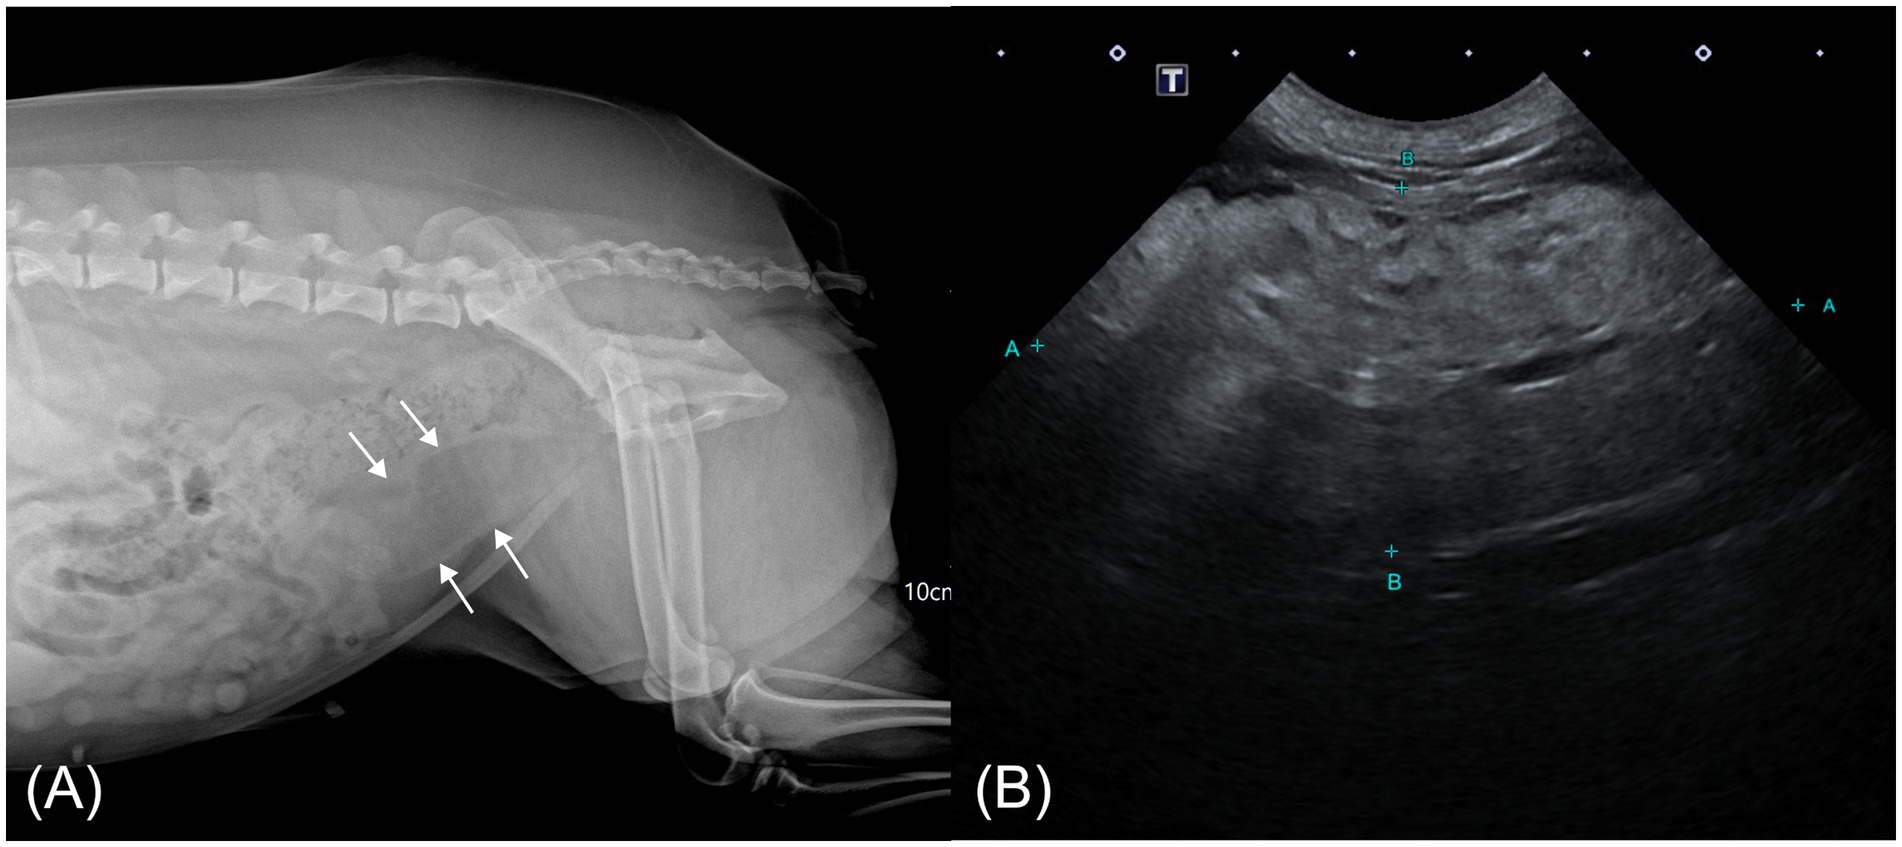

Right lateral abdominal radiography revealed a tubular structure with soft tissue opacity at the margins and radiolucent content located ventral to the descending colon, extending cranially from the pelvic cavity and partially superimposed over the urinary bladder (Figure 1A). Based on its location and the clinical context, a uterine abnormality was suspected, prompting transabdominal ultrasonography (Aplio i700; Canon Medical Systems, Japan). The ultrasound showed normal ovaries and mild thickening of both uterine horns. A small volume of fluid was present within the cervical lumen. Cranial to this region, an oblong mass, presumed to be the uterine body, was identified. The mass was predominantly homogeneously hyperechogenic with scattered, short, linear hypoechoic foci and exhibited minimal vascularity on color Doppler imaging. The connection between the mass and the ventral uterine wall was indistinct (Figure 1B).

Figure 1. Abdominal radiographic and ultrasonographic image of a case of hyperplastic cervical polyp with lipomatous differentiation in a dog. (A) Right lateral abdominal radiograph showing a radiolucent tubular mass with soft tissue margins ventral to the colon (white arrow). (B) Transabdominal ultrasonographic image showing an oblong, predominantly hyperechoic mass cranial to the vagina with scattered linear hypoechoic foci.